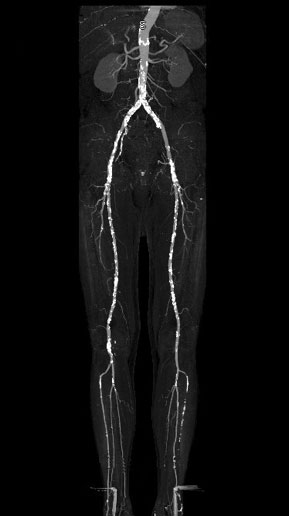

< Volver a "Tomografía Computarizada (TC) con Inteligencia artificial"Está indicado para el estudio de la patología arterial, descartar aneurismas o malformaciones vasculares, e incluso para la planificación del tratamiento con stents, entre otras aplicaciones.

En este estudio es necesaria la inyección por vena de contraste yodado, que nos aportará información sobre la luz y el calibre de las diferentes arterias.